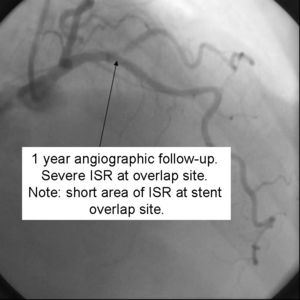

Despite excellent initial angiographic results, side branch restenosis is still a significant problem with Crush stenting(Up to 25% without kissing ballon inflation). However,most of the restenosis is silent. The above example used Cypher drug eluting stents in the Side branch and Parent vessels. The patient returned with positive stress testing 13 months later. Repeat angiography demonstrated a short segment of significant in-stent restenosis.